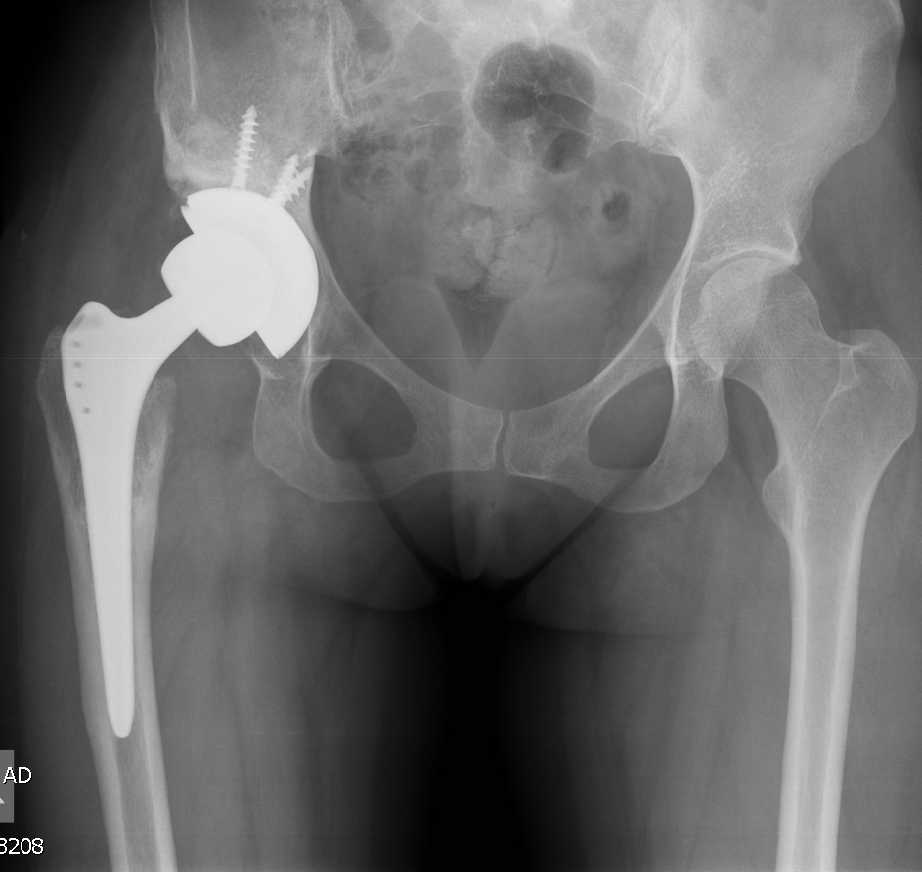

- Ендопротезиране на колянна и тазобедрена става

През октомври 1997 г. започнах работа в „Клиника по ортопедия и травматология“ в болница „Царица Йоанна“, ИСУЛ. В клиниката имах възможността да се уча и да работя с едни от най-добрите в своята област, с доц.Бинка Попова по въпроси от микрохирургията и хирургия на ръката и проф.Тивчев в областа на ендопротезиране на стави, асептични костни некрози и травматология.

Основно лекувам заболявания на тазобедрена и колянна става чрез минимално инвазивно ендопротезиране, следтравматични и дегенеративни нарушения на ръката и китката и халукс валгус (популярен като „кокалчета на краката”).